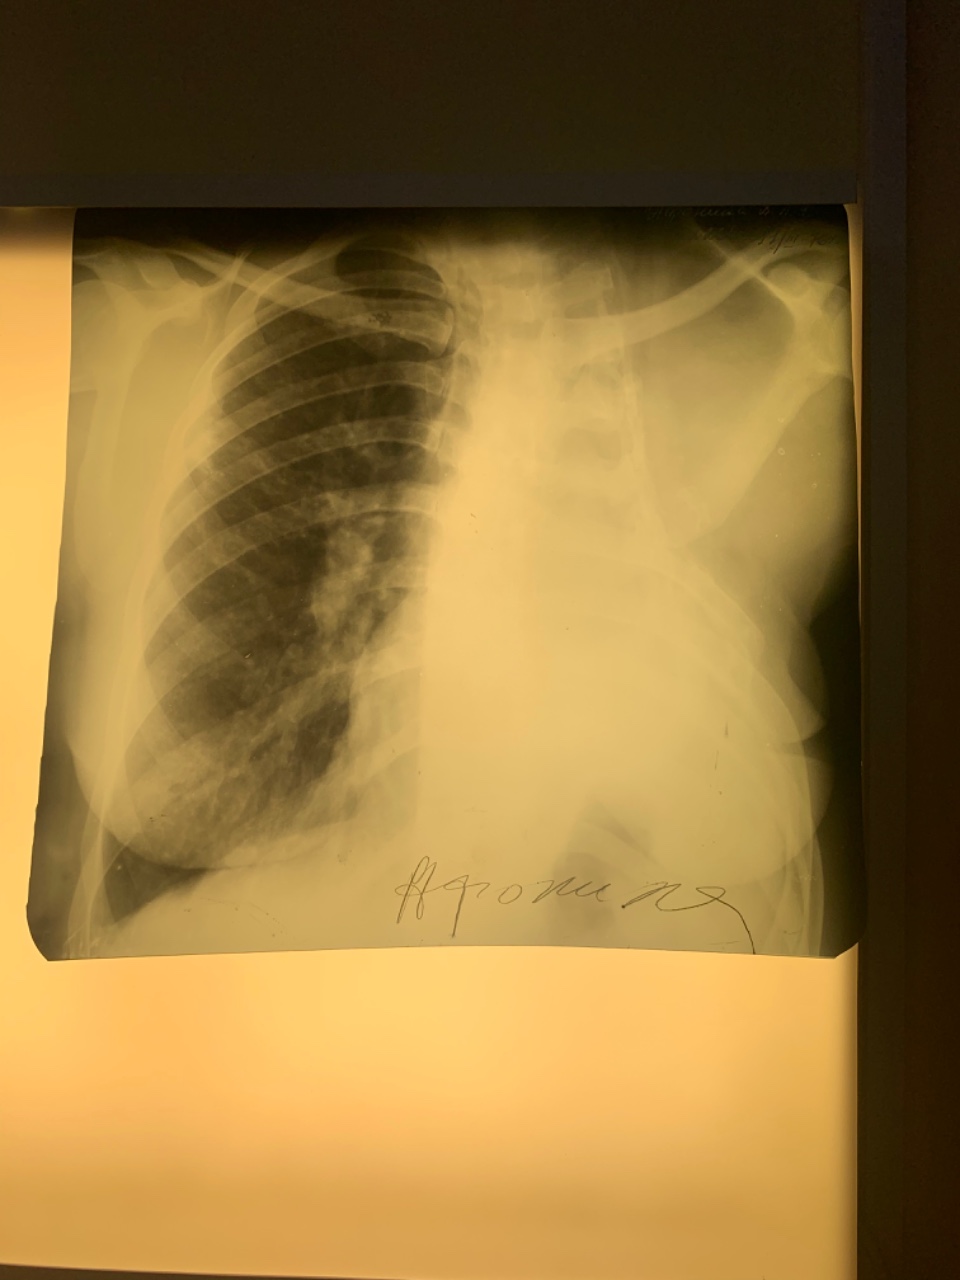

Организация рабочего пространства: стенды для рентгеновских снимков